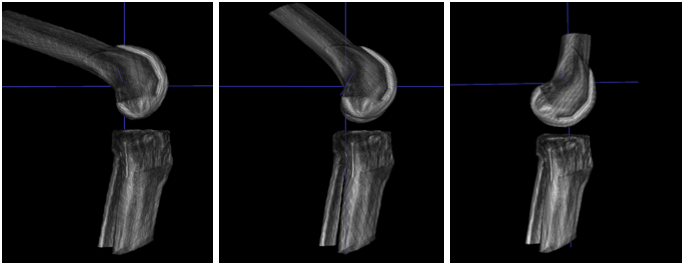

Static 3D CBCT volumes were acquired using a high-precision scanner (First-Imaging Jishuitan System), with corresponding 2D fluoroscopy images (pixel spacing 2.1 mm, resolution 1024 × 1024), as shown in Figure 4.

Refer to caption

Figure 4: Lamb knee joint clinical trial scenario